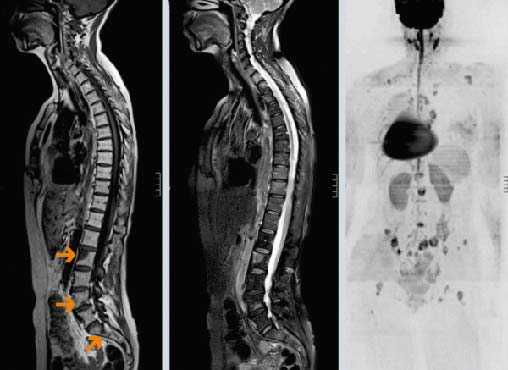

Метастазы в позвоночнике

Метастазы в позвоночнике – это очаги злокачественного поражения в костной ткани, образованные раковыми клетками, отделившимися от первичной опухоли и распространяющимися в организме с током крови или лимфы. По статистике, метастазы составляют 90% всех злокачественных новообразований в позвоночнике. Они нарушают опорную функцию позвоночного столба, способны привести к сдавлению спинного мозга, нервных корешков, тяжелым неврологическим нарушениям.

Многие типы рака метастазируют в кости, чаще всего в позвонки. В большинстве случаев опухолевые клетки распространяются гематогенно — с током крови. Вторичные очаги ослабляют костную ткань, это грозит патологическими переломами позвонков, которые приводят к сильным болям, существенному снижению качества жизни, сдавлению спинного мозга и нервных корешков.

В 95% случаев метастазы в позвоночнике являются экстрадуральными, то есть находятся за пределами твердой мозговой оболочки. Более чем в половине случаев очаги локализуются на разных уровнях позвоночного столба.

Диагностика метастазов в позвоночнике

Основные методы диагностики — КТ и МРТ. Они помогают детально визуализировать структуры позвоночного столба, опухолевую ткань. Рентгенография менее информативна, так как на снимках видны только костные структуры, обычно ее применяют при подозрении на патологический перелом.